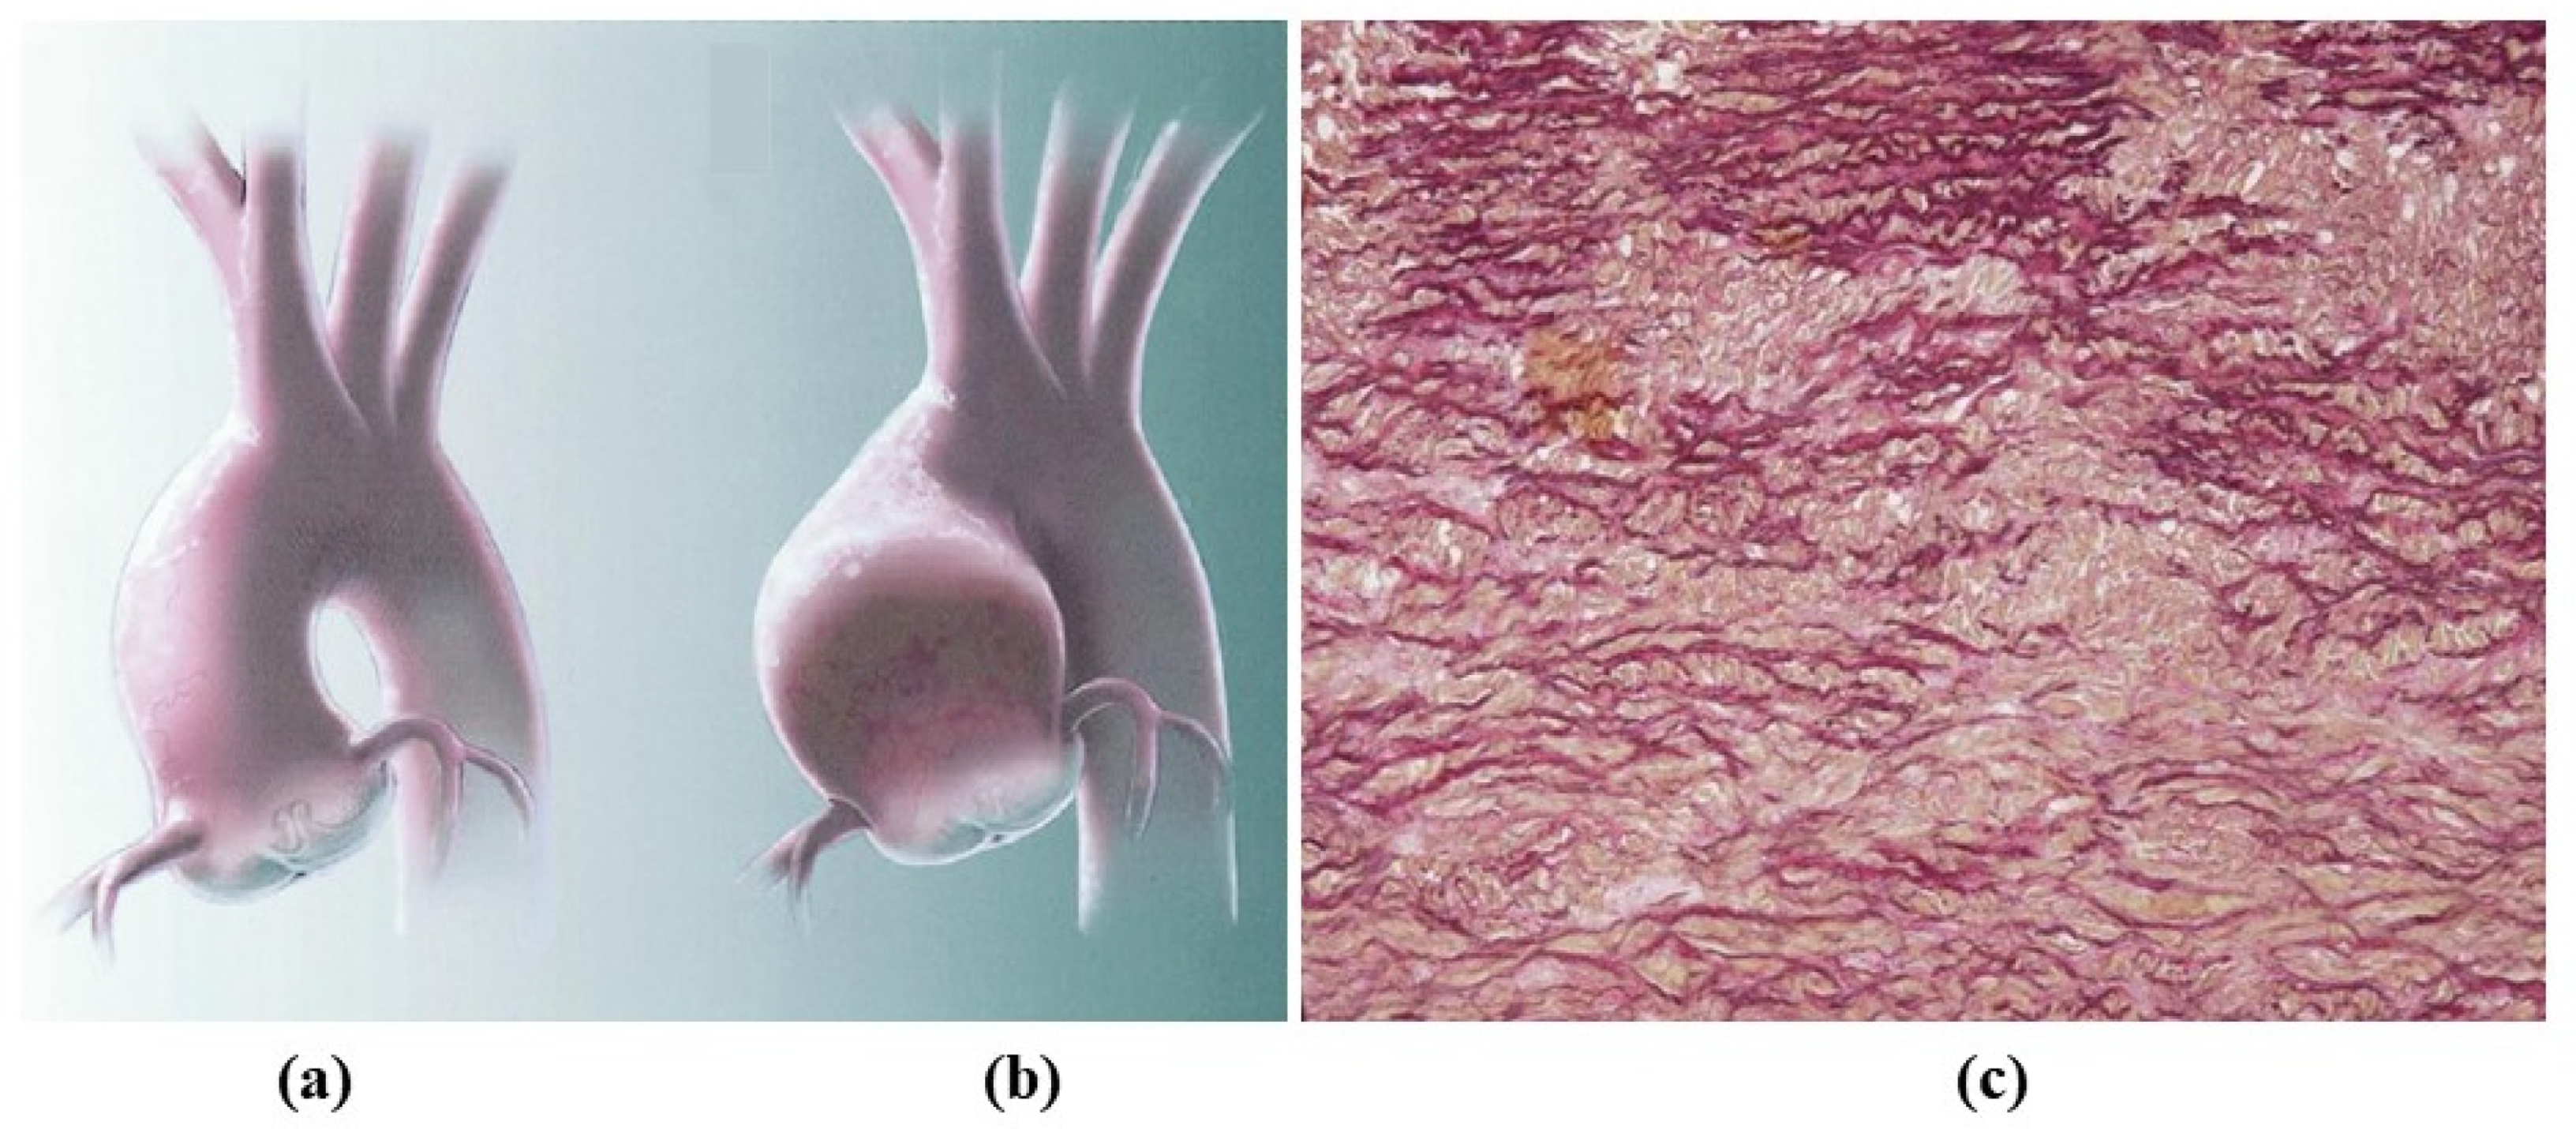

2. Normal Anatomy

3.2. Genetically Determined Diseases of Thoracic Aorta

3.3. Degenerative Diseases of the Aorta